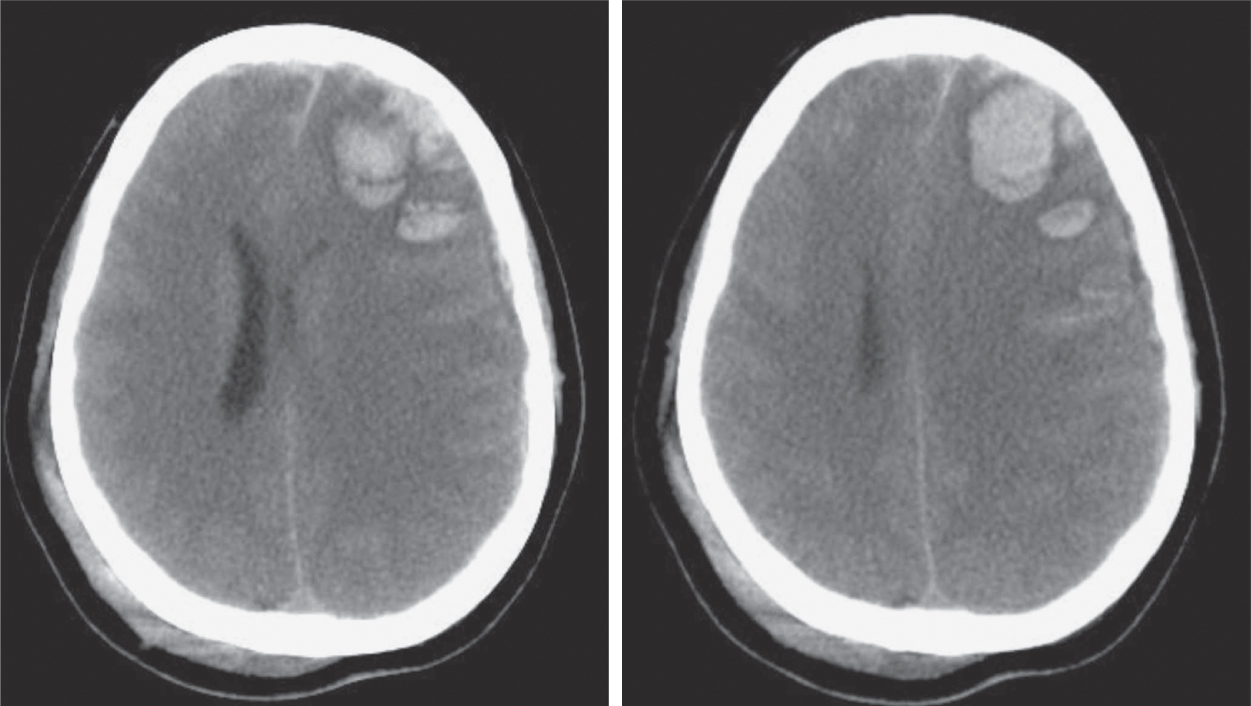

Hình 43.3 Hình ảnh CT scan cho thấy đụng dập xuất huyết gây lệch đường giữa (Amy K. Wagner, Kevin Franzese, Justin L. Weppner, Christina Kwasnica, Gary N. Galang, Jason Edinger, Mark Linsenmeyer. Chapter 43 Traumatic Brain Injury, Editor(s): David X. Cifu, Braddom’s Physical Medicine and Rehabilitation (Sixth Edition), Elsevier, 2021, Pages 916-953.e19, ISBN 9780323625395.)

Hình 43.4 Hình ảnh CT scan cho thấy tổn thương sợi trục lan tỏa (DAI) sau khi bệnh nhân bị chấn thương sọ não nặng Mặc dù thường khó nhìn thấy trên CT scan, DAI dẫn đến các tổn thương lan rộng trong các đường dẫn chất trắng và có thể được nhận thấy khi các xuất huyết nhỏ hình thành gần các sợi trục bị cắt đứt.